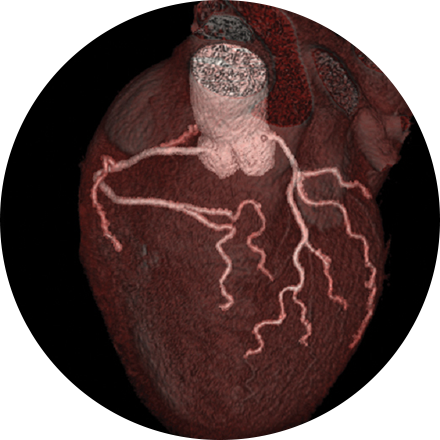

Coronary Artery Calcium Scoring

This exam is part of a sophisticated high-speed CT exam of the heart. During the scan, which takes just seconds, the equipment measures the amount of calcium present and calculates a score. The lower the score, the lower the potential risk of an adverse future cardiac injury. (Calcium often covers the atherosclerotic plaque that builds up inside arteries. This plaque and calcium can lead to narrowing of the inside of the arteries which could in turn lead to an increased risk of angina, and a heart attack.) This test can assess coronary heart disease, which is often asymptomatic and is the most common cause of death for patients in the United States.